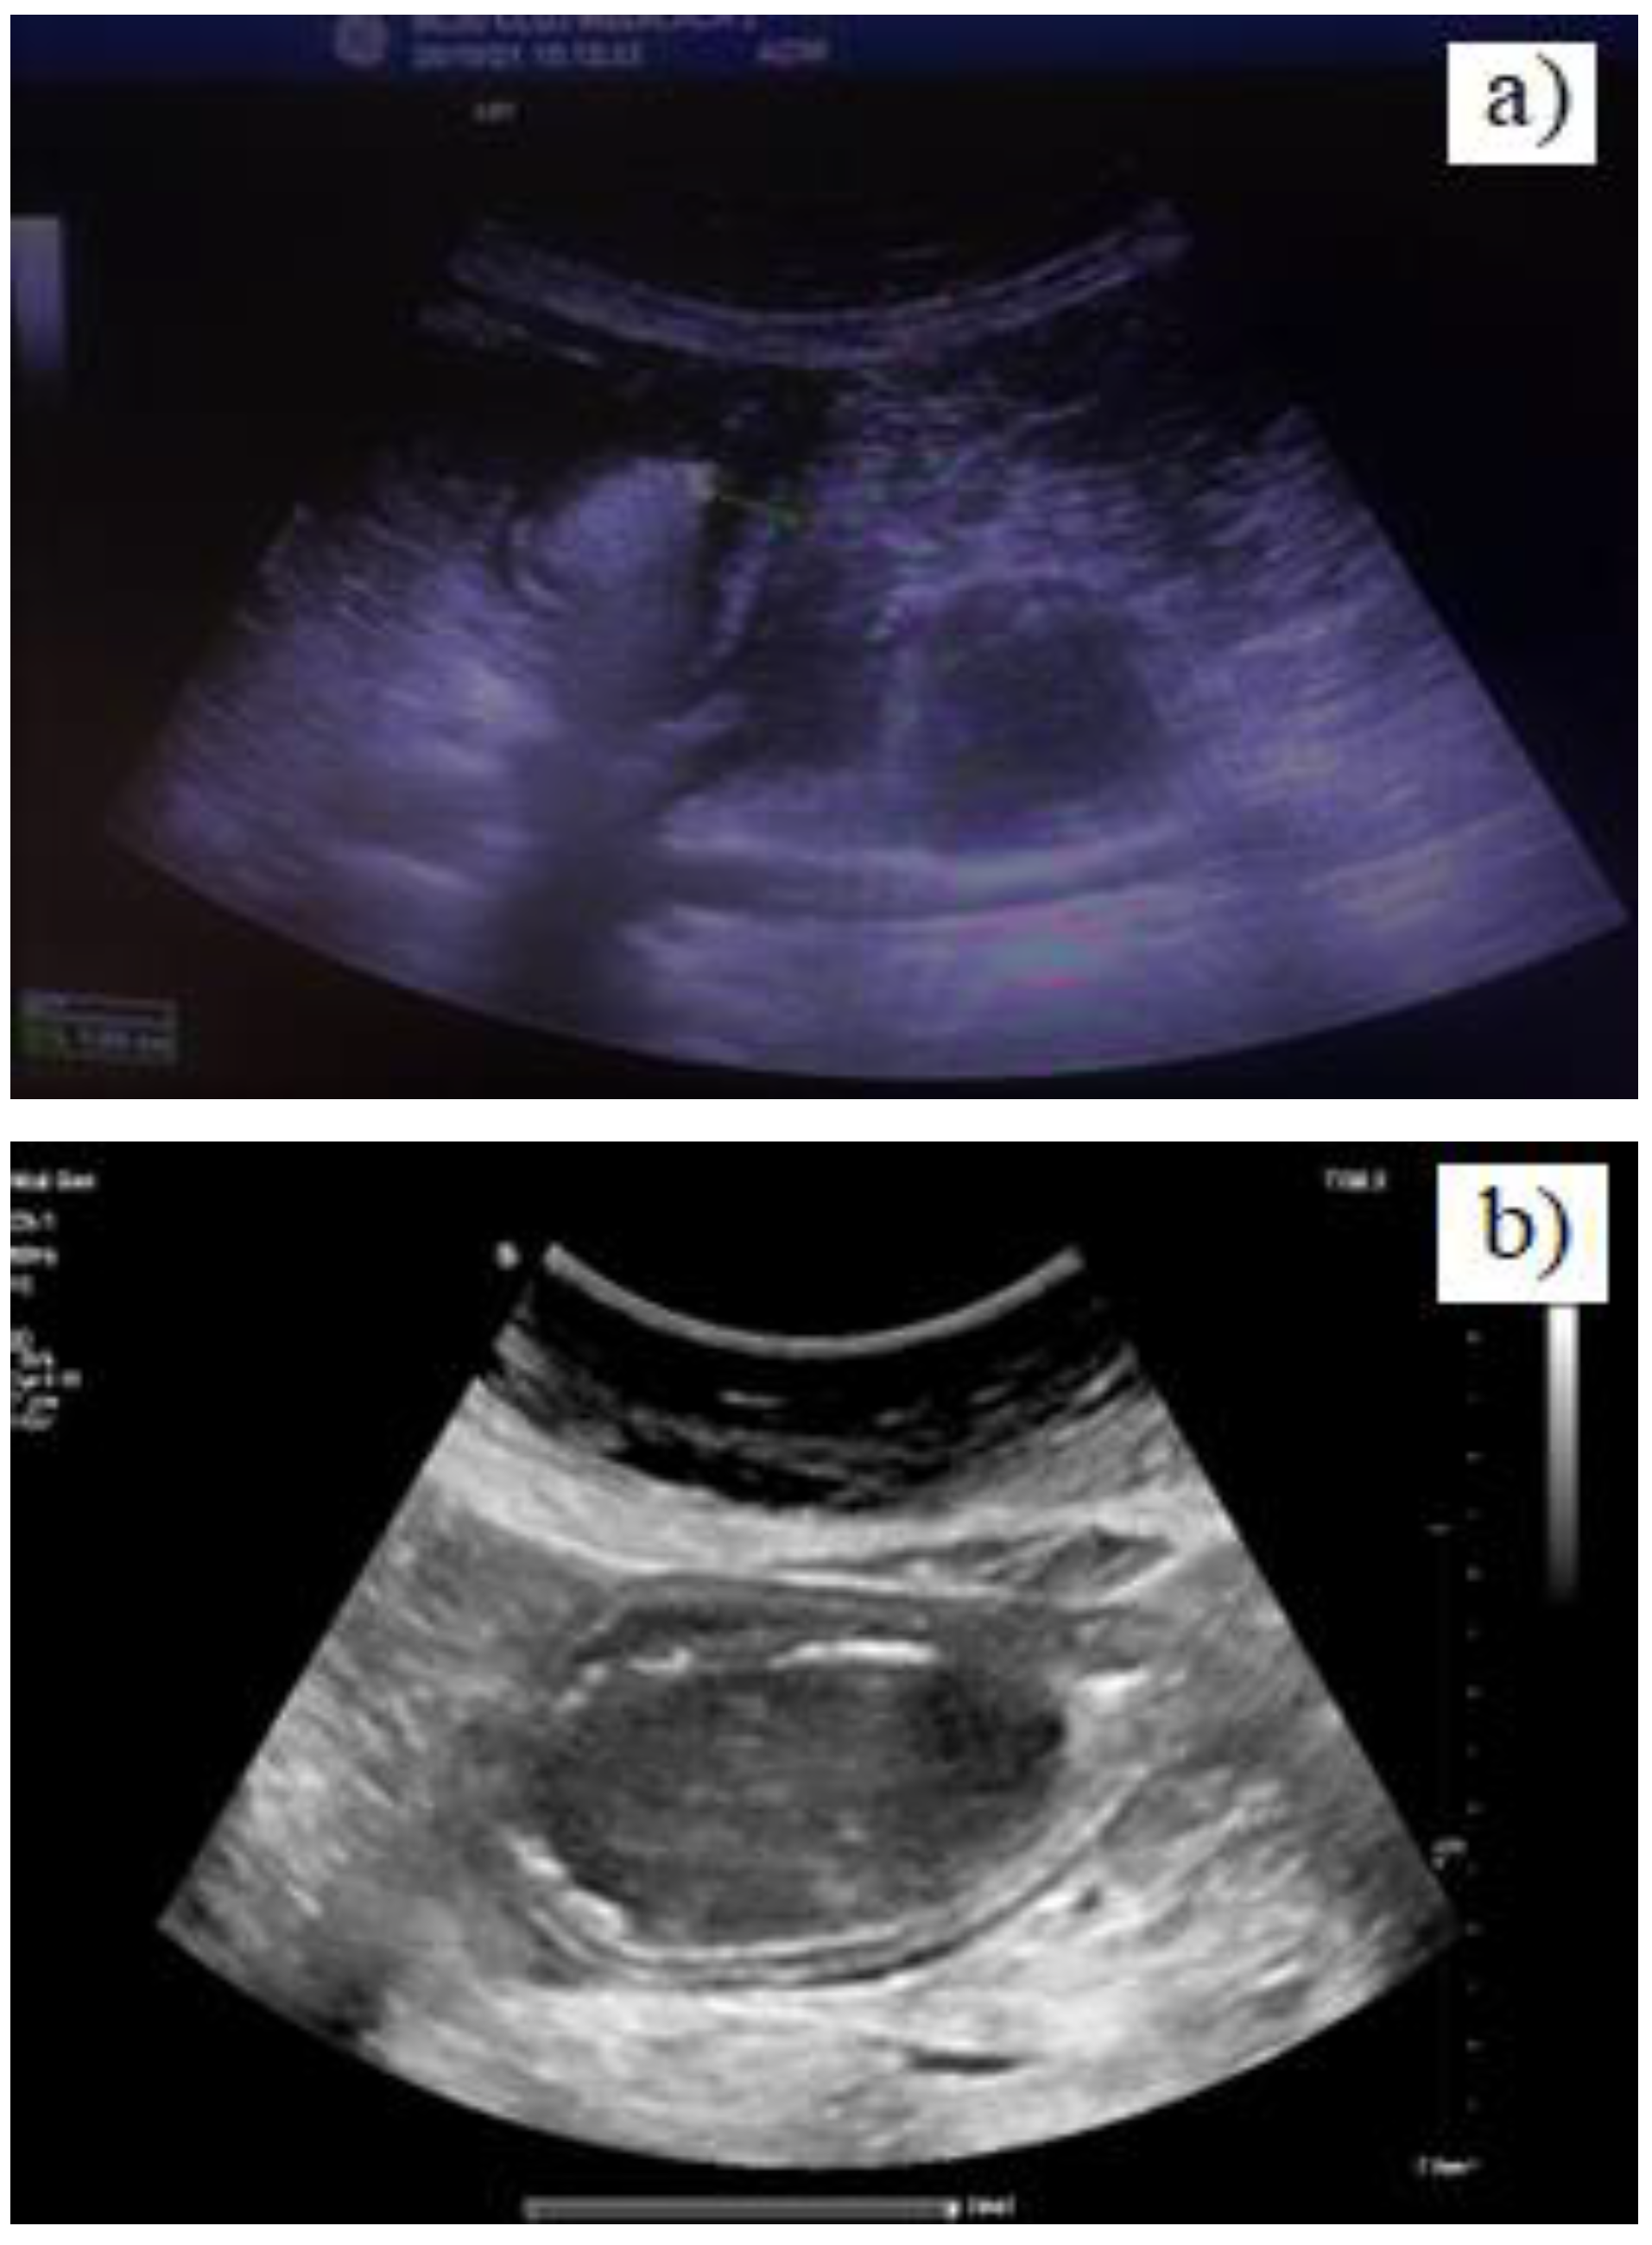

Case presentation